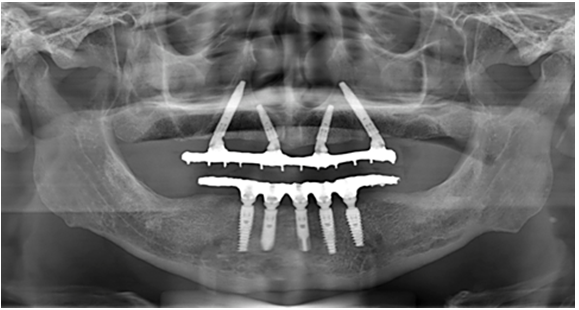

Dois implantes são instalados na região anterior, geralmente de forma axial, enquanto os dois implantes posteriores são posicionados com inclinação distal, normalmente entre 30° e 45°.

Essa angulação permite o melhor aproveitamento do osso disponível nas regiões anteriores da maxila ou mandíbula, evitando áreas de maior reabsorção óssea posterior, como o seio maxilar e o canal mandibular.

A avaliação clínica deve ser complementada por exames de imagem, especialmente a tomografia computadorizada, que permite analisar volume ósseo, densidade, relações anatômicas e angulações ideais.